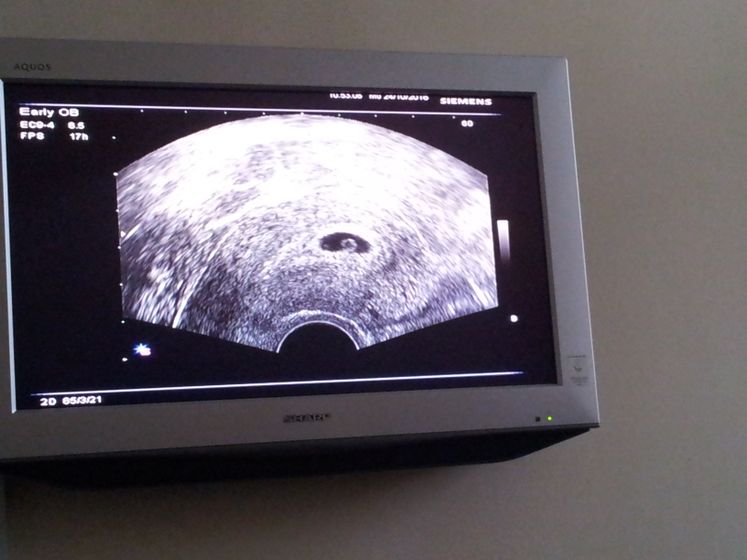

Всем привет! Только что приехала с женской консультации. Было первое узи. Все слава Богу в норме. Беременность маточная, плод соответствует сроку 4 недели и 4 дня. Даже видела как бьется сердечко манюнечки.